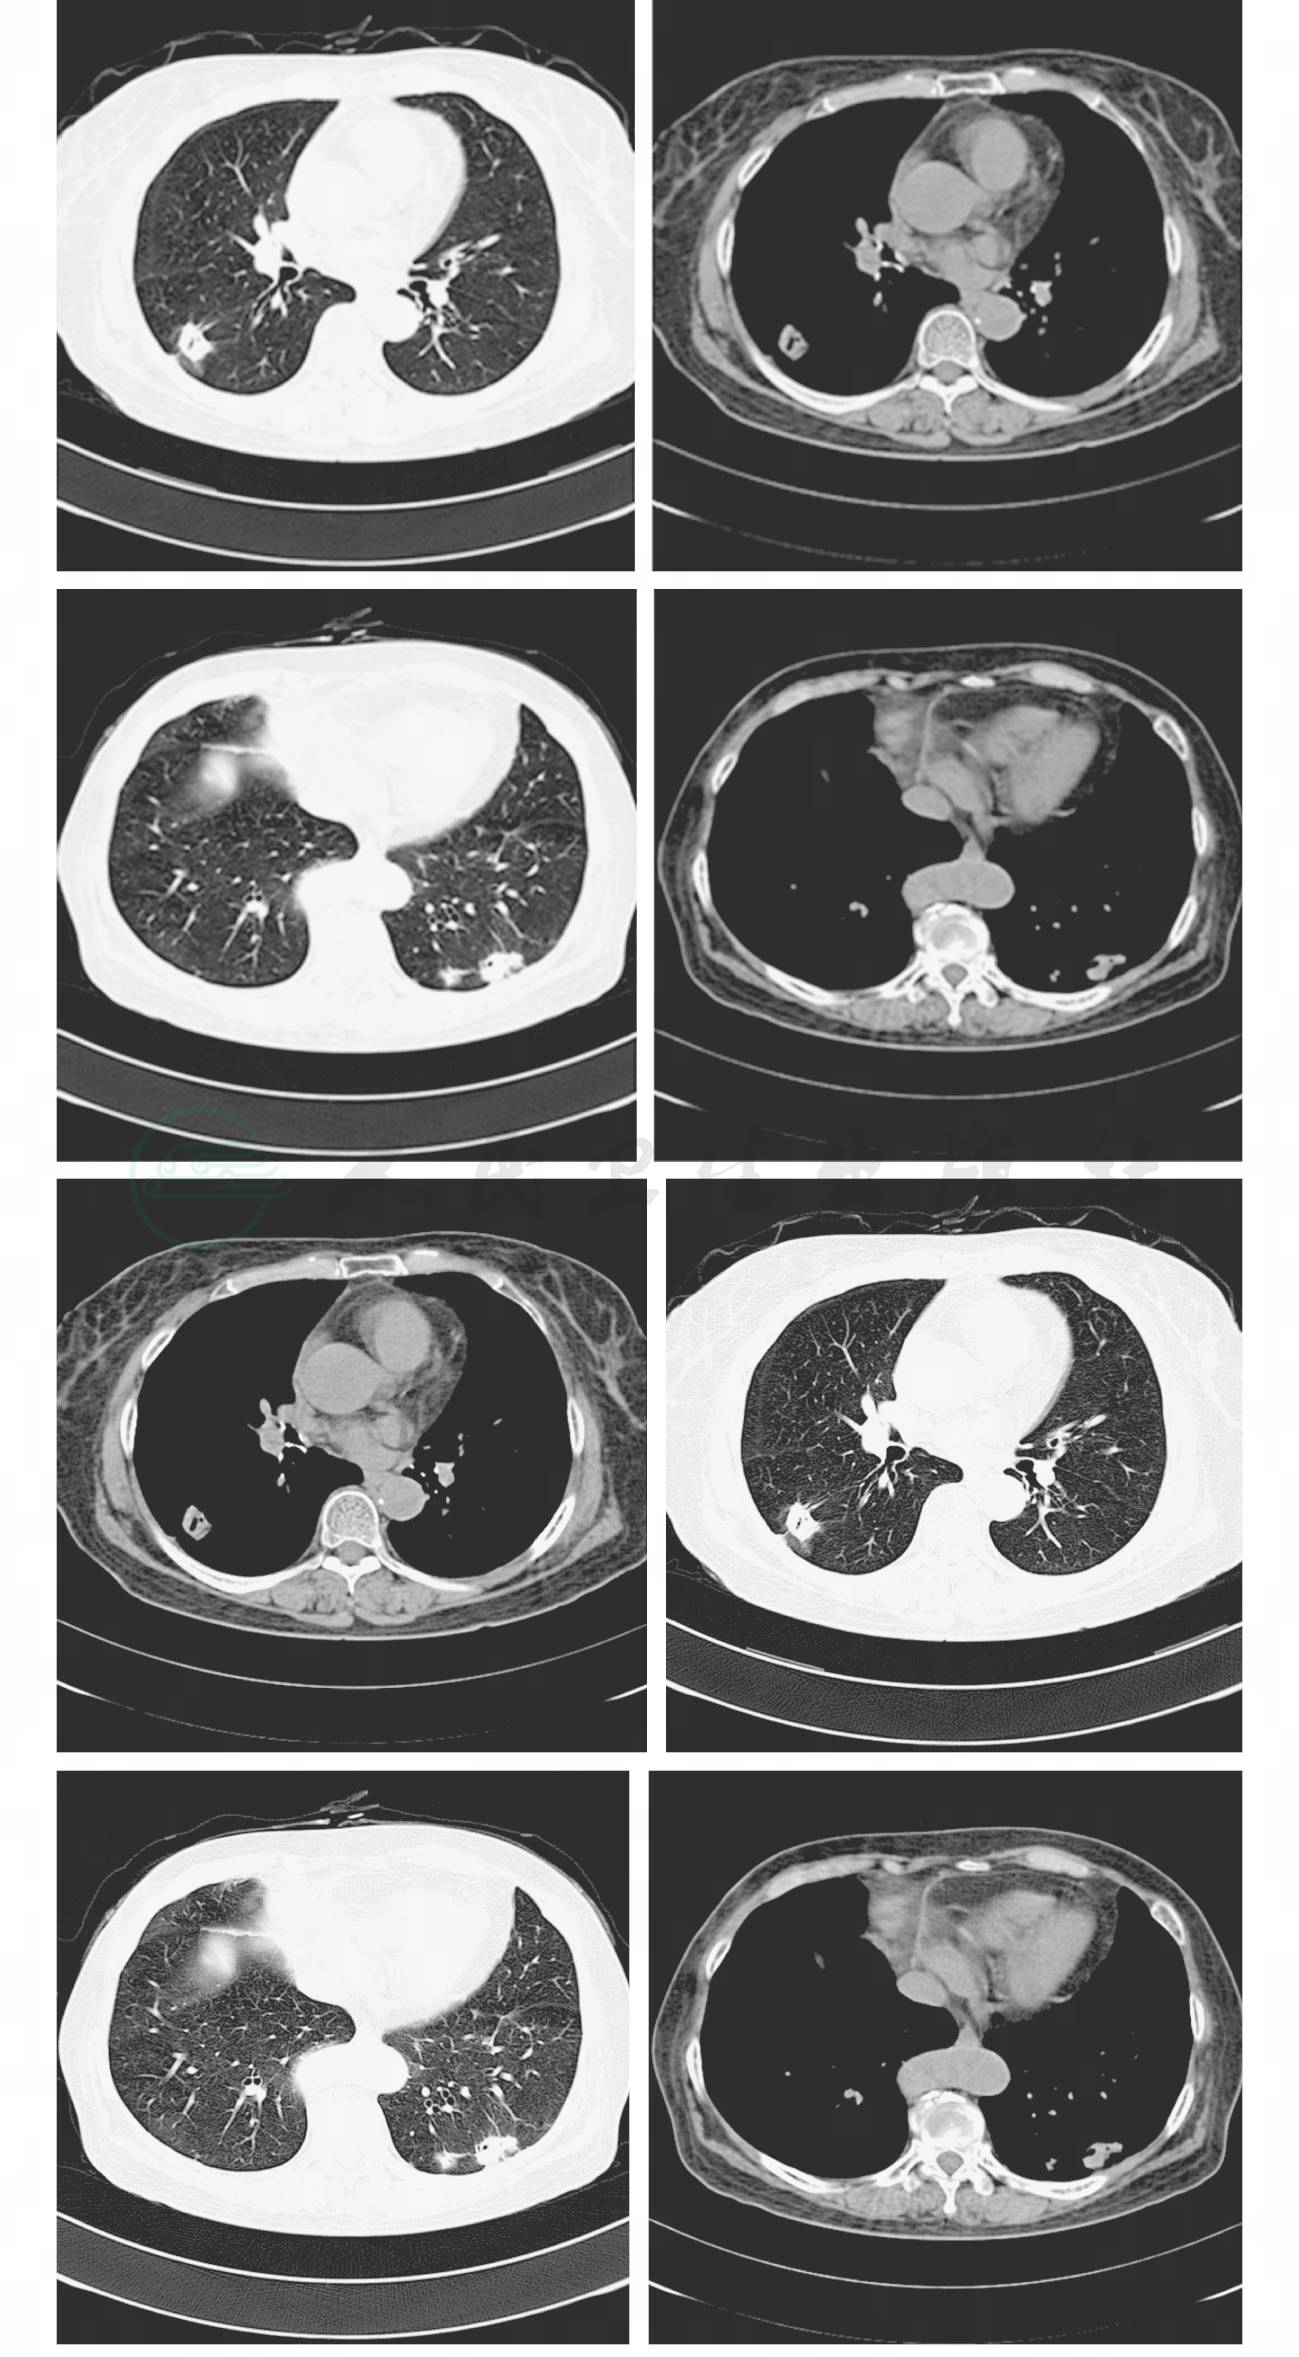

病程中无咳嗽、胸痛、咯血和呼吸困难,无发热、畏寒,无潮热、盗汗。既往患类风湿性关节炎5年,长期服用泼尼松、甲氨蝶呤 。胸部CT(2008年07月11日)示右肺下叶上段见一直径约2.3cm结节,可见血管聚集、胸膜凹陷、细支气管截断及空泡。左肺下叶后基底段见片团影,可见血管聚集、细支气管截断及胸膜凹陷,该片团影内侧方尚见一小结节影。气管、支气管通畅,肺门、纵隔淋巴结未见增大(图1)。PET-CT(2008年07月11日)示右肺下叶上段占位性病变,FDG代谢活跃(最大SUV值3.5),延迟显像见病灶代谢活跃度明显增加(最大SUV值4.1),考虑为肺部恶性肿瘤可能性大;左肺下叶后基底段可见软组织密度占位,FDG代谢明显异常活跃(最大SUV值8.3),延迟显像见代谢活跃度明显增加(最大SUV 值11.8),考虑恶性肿瘤可能性大(图2)。

图1 胸部CT(2008-07-11)示右肺下叶上段见一直径约2.3cm结节,左肺下叶后基底段见片团影,该片团影内侧方尚见一小结节影

图2 PET-CT(2008-07-11)示右肺下叶背段和左肺下叶后基底段可见软组织密度占位,FDG代谢明显异常活跃,延迟显像见代谢活跃度明显增加

治疗4个月后(用药期间停用泼尼松、甲氨蝶呤),患者因类风湿性关节炎加重于2008 年11月27日第2次入院,入院后复查胸部CT(2008年11月28日)示右肺下叶上段、左肺下叶后基底段出现新的片团影(图5)。考虑抗结核治疗无效,病情进展。为了进一步明确诊断,重新阅读患者术后病理切片报告:双肺结节肉芽肿性炎伴坏死,抗酸染色未查见抗酸杆菌,PAS染色见肉芽肿内有大小不一的真菌孢子(图6)。病理学诊断:肺隐球菌感染所致肉芽肿。

图5 结核治疗4个月(2008-11-28)胸部CT示右肺下叶上段、左肺下叶后基底段出现新的片团影

治疗与转归:2008年12月7日调整治疗,给予抗真菌治疗:氟康唑0.4g,每天1次,共15天;氟康唑0.3g,每天1次,共15天;氟康唑0.15g,每天1次,共30天。抗真菌治疗4周后复查胸部CT(2009年01月05日)示右肺下叶上段、左肺下叶后基底段片团影明显吸收好转,残留部分纤维条索影(图7)。抗真菌治疗3个月后复查胸片示肺部未再出现新的感染灶(图8)。抗真菌治疗3个月后停药。

图7 胸部CT(2009-01-05)示右肺下叶上段、左肺下叶后基底段片团影明显吸收好转,残留部分纤维条索影